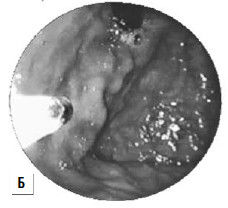

Баллонная тампонада зоны кровотечения позволяет временно его остановить, после этого проводится гемостатическая терапия и восполняется кровопотеря. Через сутки давление в баллонах снижают. При остановке кровотечения могут быть предприняты попытки эндоскопической профилактики кровотечения путем паравазальной склеротерапии (при этом эффективность метода составляет около 90 %, а рецидивы кровотечения возникают почти в 30 % случаев) или эндоскопического лигирования вен пищевода (рис. 85; рис. 87).

Рис 87. Паравазальное склерозирование. А) момент операции; Б) результат операции